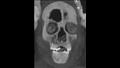

وأوضحت الدكتورة سحر سليم أن المومياء لصبي توفي عن عمر يناهز 15 عاما وأنه تم تحنيطها بإتقان كبير، وتم إزالة المخ من خلال فتحة الأنف ووضع الحشوات والراتنج داخل تجويف الجمجمة.

وأكدت سليم أن الدراسة كشفت عن وجه المومياء لأول مرة بعد إزالة اللفائف بشكل افتراضي بتقنية الأشعة المقطعية، حيث أتاحت الدراسة فرصة فريدة لاكتشاف أسرار تحنيط المومياء دون المساس باللفائف، وكما تركها المصريين القدماء.